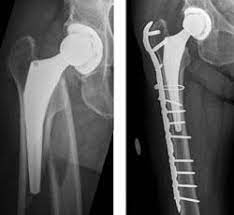

La prothèse de hanche est une des interventions majeures en orthopédie. Gr?ce au traitement antalgique, l'op?r? L'indication d'une reprise totale de hanche est portée la plupart du temps, dans le cas d'une faillite mécanique des implants.

Ainsi 150 000 prothèses de hanche et 100 000 de genou sont posées par an. Respecter la notion de reprise tr s progressive. Fracture du fémur prothésé (chute).

Descellement et usure de l'implant. Learn new and interesting things. Cette pratique présente des avantages mais aussi des risques !

La nécessité d'une prothèse de hanche intervient pour diverse raison. Fracture du fémur prothésé (chute). Complications tardives des proth2ses de hanche.